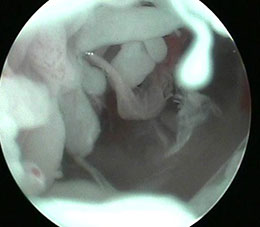

针刀镜技术利用其独有的高清内窥镜,在手术过程中可全面直观的鉴别诊断相关病情,尤其是用于非感染关节炎的鉴别,根据关节滑膜的充血和水肿、关节软骨损伤程度及关节内有无游离体等病理改变可协助鉴别类风湿性关节炎、骨性关节炎及痛风性关节炎等疾病。还可用于关节及软组织结构急慢损伤的观察诊断,同时用于提取各病变组织的活检标本,避免检查的二次伤害。

针刀镜技术是在无菌环境下,由专业操作医生,利用针刀镜操作设备及内窥镜,进行可视化操作。针刀镜治疗切口小于0.4厘米,在治疗过程中,专业操作医生利用通道可进行局部剥离、灌洗、注射、置药等多项操作。快速剥离和疏通关节及病变组织,解除粘连,消除炎症,恢复关节功能,以达到临床快速诊治风湿骨病的治疗目的。

针刀镜治疗利用影像设备进行可视操作,减少了治疗的危险性、提高了成功率;治疗部位深入,剥离和疏通彻底。